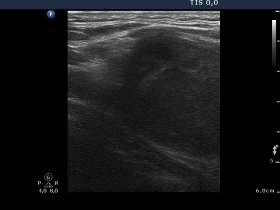

Ultrasonography revealed that the palpable mass contained the enlarged left thyroid composed of a large hypoechogenic nodule with irregular borders and multiple irregular lymph nodes in the left side of the neck.